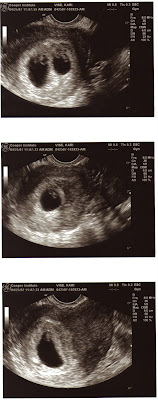

The top photo is both.

The center and bottom are their individual portraits....